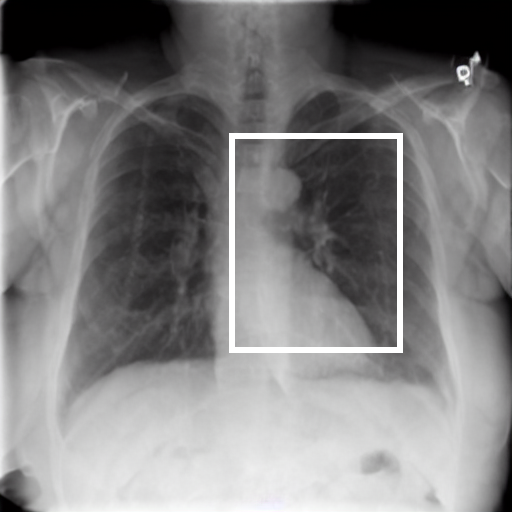

We therefore illustratively test our model in regard to its latent capability to induce disease in specific locations through the simple expedient of conditioning on positionally-indicative text. The results may be seen in figure 7 for the case of localized lung opacity (lung opacity being chosen because it is both diffuse and generally specific to one or other lung). The respective condition texts are “large lung opacity on the left” and “large lung opacity on the right”.